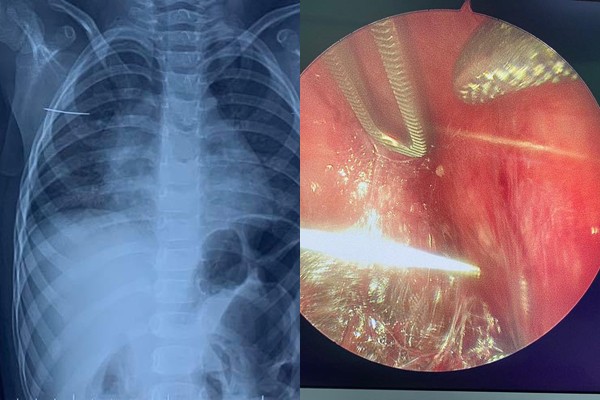

Sáng hôm sau, cháu vẫn kêu đau dù bên ngoài không thấy tổn thương. Bố mẹ đưa bé đến BV đa khoa huyện thăm khám, bác sĩ chụp X-quang phát hiện có dị vật ở vùng vai phải nghi là kim khâu.

Sau khi chụp CT dựng hình, bác sĩ phát hiện dị vật dạng kim khâu nằm ở thành ngực bên phải, phía sau xương bả vai, kèm theo có ổ dịch khí viêm nhiễm xung quanh.

Theo tính toán ban đầu, kim nằm trong thành ngực phải, chưa di chuyển hẳn vào trong khoang màng phổi nên bác sĩ dùng ống nội soi, lách giữa các lớp cơ thành ngực để tìm kim, vừa đảm bảo hạn chế co kéo làm kim di chuyển, vừa là phẫu thuật ít xâm lấn, đường mổ nhỏ cho tầm quan sát lớn. Nếu cần có thể nội soi luôn vào trong khoang ngực để quan sát.

Trong quá trình phẫu thuật nội soi, bác sĩ dùng 3 trocar đi vào tổ chức giữa cơ dưới vai và cơ thang, quan sát thấy chiếc kim nằm lẫn trong các sợi cơ. Sau 1 giờ, chiếc kim được lấy ra nguyên vẹn, không đứt gãy.